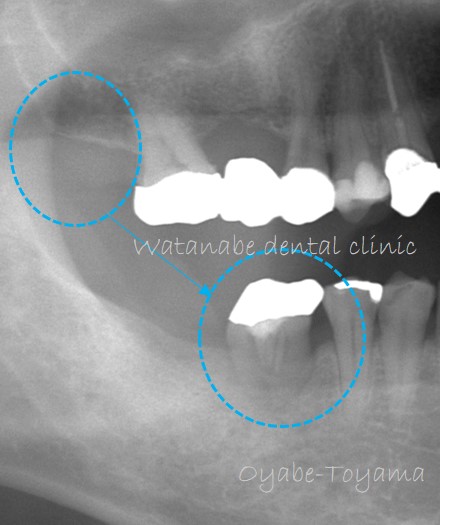

今回も親知らずの移植です。

オレンジ〇部分の歯が喪失しています。そして、青○が親知らずです。この親知らず(青○)と咬んでいる歯は無く、余っている状態です。このまま親知らずを残しておいても抜歯するしかありません。

このまま親知らずを抜歯してしまうのが勿体ないので、この親知らず(青○)をオレンジ○部分へ移植する計画としました。

下写真は移植直後の状態です。

移植した歯は歯の中の歯髄(血管、神経線維、細胞が入っている組織)が失活してしまうため、根管治療(歯髄が入っている組織を消毒すること)を行い、冠を被せていきます。

冠を被せた状態です(下写真)。これで、咬めるようになりました。

今のところ良好に経過しています。